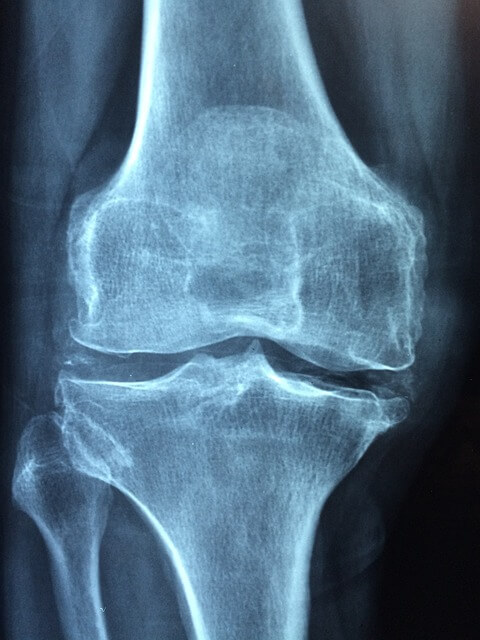

골다공증은 뼈의 밀도와 강도가 저하되는 질환으로, 골조직의 손실로 인해 뼈가 취약해지고 쉽게 부러질 수 있는 상태를 말합니다. 주로 고령자에게서 발생하지만, 어린이나 성인도 골다공증에 걸릴 수 있습니다.

골다공증은 뼈 손실이 비교적 빠르게 진행되기 때문에 "침묵의 질병"이라 불리기도 합니다. 실제로 증상이 나타나기 전에는 대부분의 환자들이 자신이 골다공증에 걸렸음을 알지 못합니다. 그러나 골다공증은 뼈가 쉽게 골절되는 위험을 증가시키므로, 중요한 질환이라고 할 수 있습니다.

골다공증 증상

골다공증은 뼈의 밀도가 감소하여 뼈가 약해지는 상태를 말합니다. 골다공증의 주요 증상은 다음과 같습니다.

3. 골절 쉬움: 골다공증은 뼈의 약화로 인해 비교적 경미한 부상이나 충격으로도 골절이 발생하기 쉬워집니다. 특히 골밀도가 낮아진 골다공증 환자는 적은 충격으로도 골절이 발생할 수 있습니다.